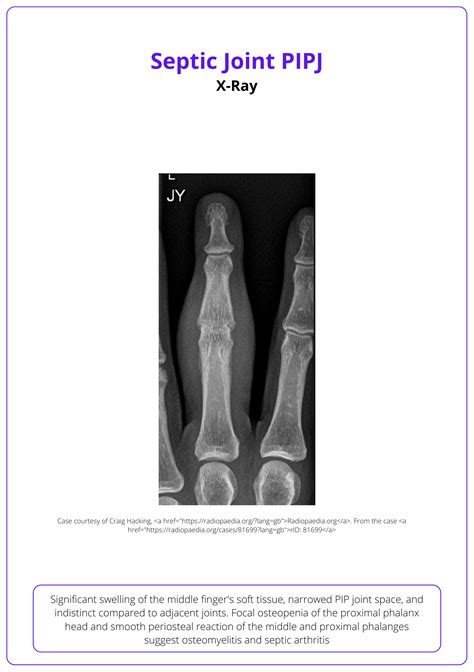

The condition is most common in the knees, but it can affect hips, shoulders, and other joints. Because the joint space is a closed, nutrient-rich environment, bacteria can multiply rapidly. This leads to the destruction of cartilage and bone if not addressed immediately. More importantly, the infection can spill over into the bloodstream, triggering a systemic inflammatory response known as sepsis.

• Osteomyelitis: The infection can spread to the surrounding bone, causing chronic, deep-seated infections that are extremely difficult to treat.